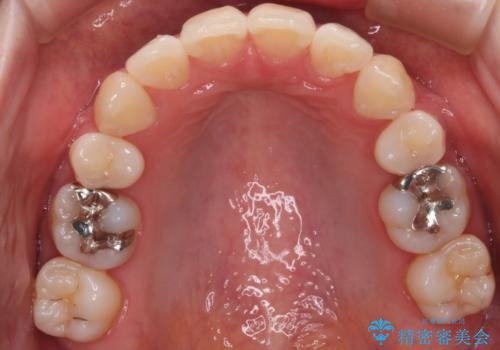

- 出っぱによる口元の閉じにくさを主訴に来院されました。上顎の出っ歯と上下顎叢生も認められたため、上下顎両側4番抜歯を行い、ワイヤー矯正で治療する治療計画を立てました。

上顎にはMI(マイクロインプラント)を埋入して固定源とすることで出っ歯の改善を図りました。

少しスペースクローズに時間がかかりましたが、MIを用いたワイヤー矯正で

主訴である出っ歯と叢生が改善されました。口も閉じやすくなり、スッキリとした口元になりました。